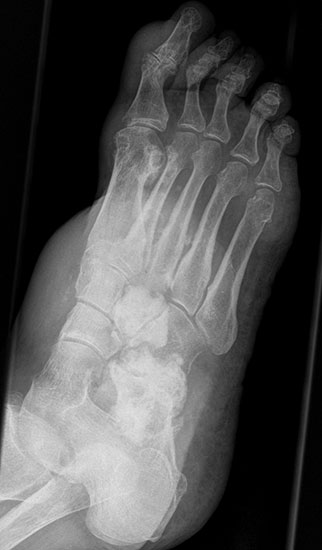

Das solitäre Enchondrom ist von Enchondromatosen, also disseminierten Enchondromen der Extremitäten und des Achsskeletts, abzugrenzen. Die Entartungswahrscheinlichkeit ist für Enchondromatosen wie dem M. Ollier (Abb. 18a und b) oder dem Maffuci-Syndrom deutlich erhöht und wird in der Literatur bis zu 25% angegeben. Klinische und radiologische Hinwiese für eine Entartung beinhalten Kortikalisveränderungen, wie -verdickung, -destruktion und die enossale Kortikalisarrosion, welche in der CT-Bildgebung mehr als 2/3 der Zirkumferenz des betroffenen (Röhren-) Knochens umfasst.